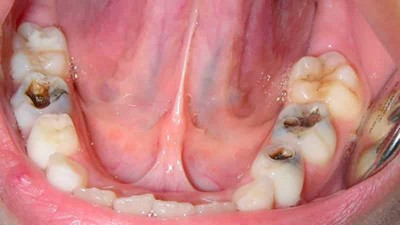

- Запущенный кариес — основная из них. С течением времени без необходимого лечения кариозная полость продолжает расширяться и углубляться, из-за чего патогенные бактерии легко проникают в мягкую зубную ткань. Проникновение происходит как напрямую, если пульпа открыта, так и по дентинным каналам.

- Низкий уровень гигиены ротовой полости, что неизбежно приводит к кариесу.

В сочетании с пищевыми остатками подобная микрофлора образует налёт.

Микроорганизмы начинают выделять кислоту, остатки пищи разлагаются, и зубная эмаль постепенно разрушается. Образуется кариес, инфекция которого с течением времени проникает в дентин (костное вещество зуба), а затем и в пульпу. В этой мягкой ткани расположено огромное количество нервных окончаний. Отёкшая воспалённая пульпа их сдавливает, что вызывает острую пронизывающую боль.